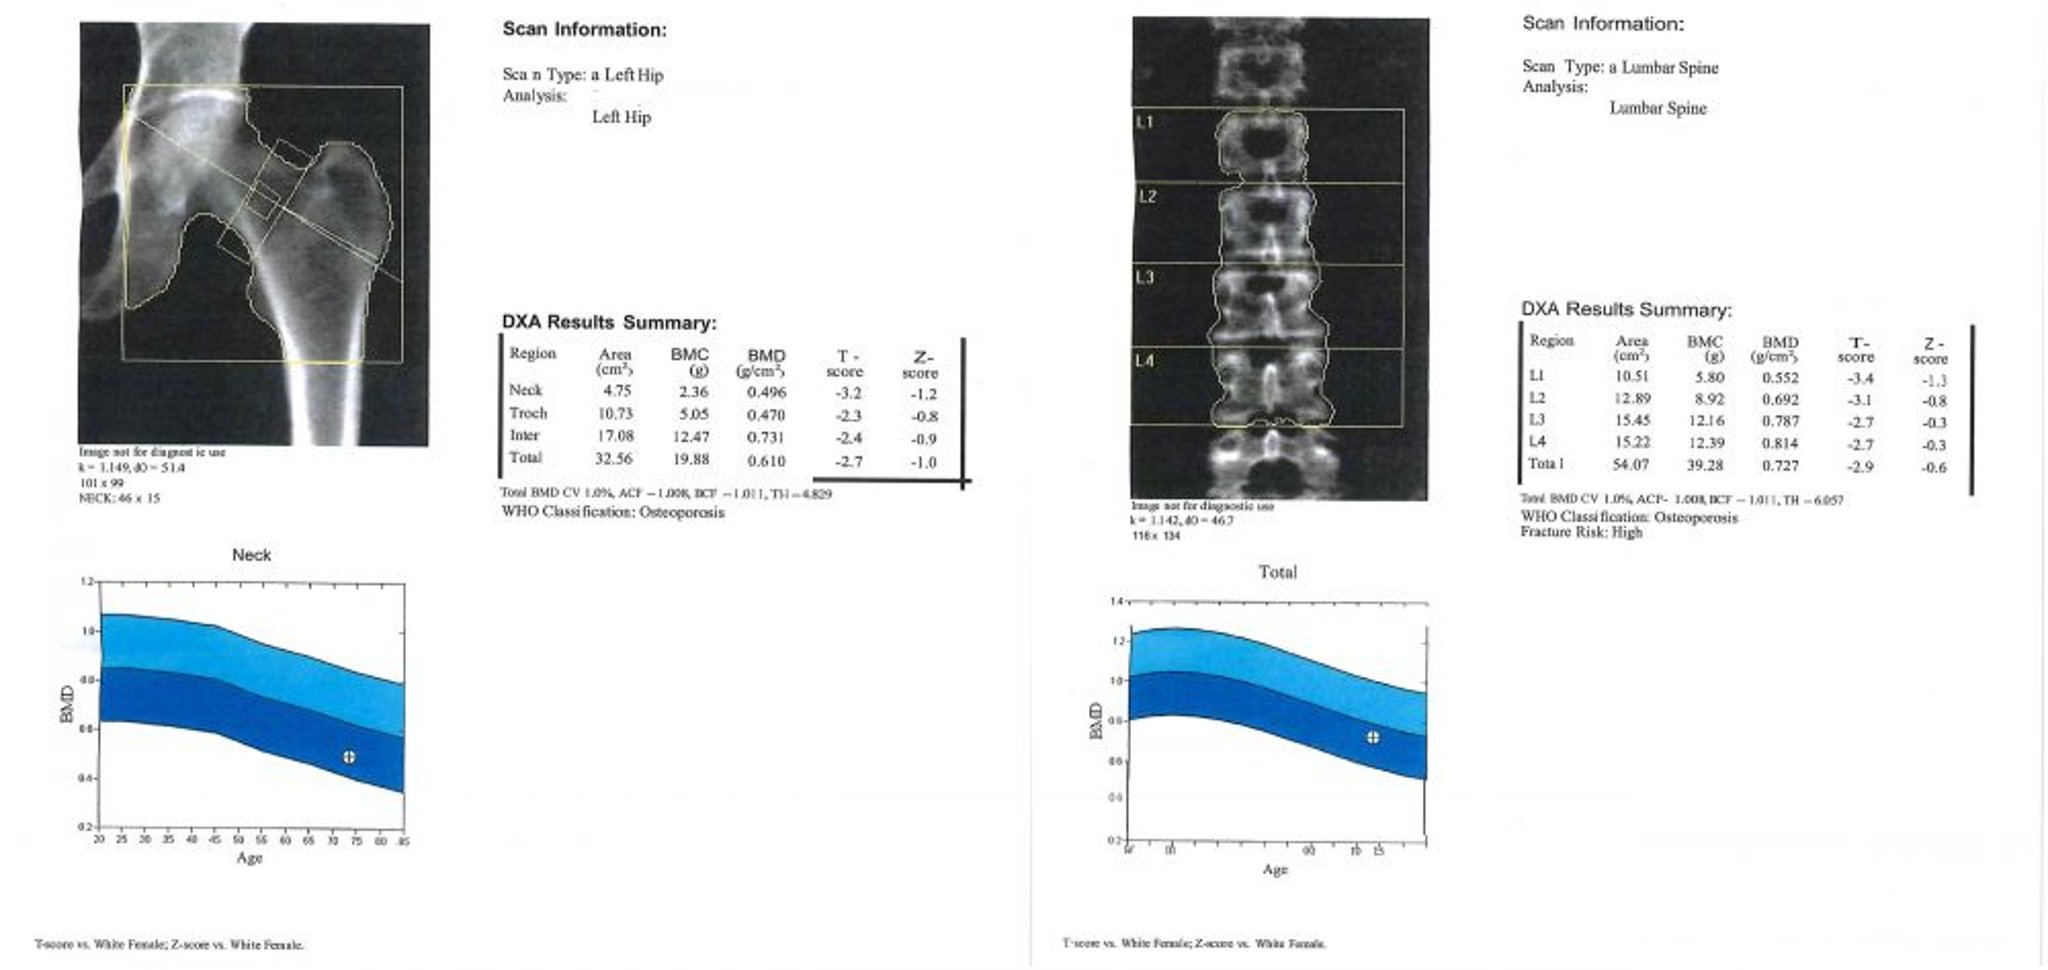

DXA scan

Cette image est un exemple de rapport de scan DXA. Dans le graphique, la zone en bleu clair représente l'ostéopénie et la zone en bleu foncé représente l'ostéoporose. Les valeurs du patient sont représentées par le signe "+" à l'intérieur du cercle dans chaque graphique.

Image courtoisie de Marcy B. Bolster, MD.